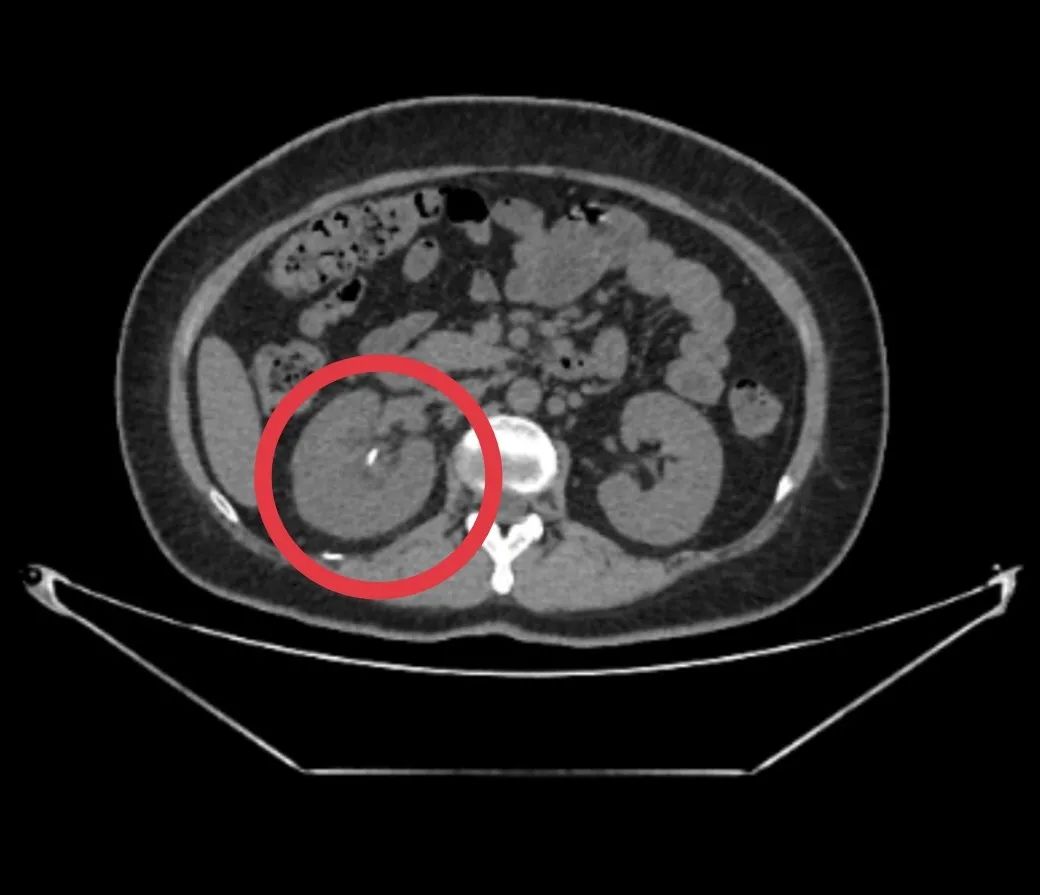

许女士(化名)的经历,为我们敲响了输尿管内支架规范管理的警钟。一年多前,她因右侧输尿管上段结石合并肾积水就诊,却恰逢早期妊娠无法手术,医生为其植入输尿管内支架以缓解梗阻。然而,因未按时返院更换,如今再次就医时,CT 检查显示支架上已附着大量结石,形态如同 「棒槌」—— 这正是支架长期留置引发的典型问题。

面对复杂情况,许女士来到了漳州第三医院泌尿一科,陈川聪主任带领团队制定了精准的手术方案:通过「经尿道膀胱结石钬激光碎石取石术」「经尿道右侧输尿管软镜联合钬激光碎石取石术」及「经尿道右侧输尿管内支架取出术」,分步骤处理病灶。术中可见,右侧双 J 管(输尿管内支架的常用类型)头端已被直径约 4.0 cm×3.0 cm 的膀胱结石完全覆盖,医生先将膀胱内结石击碎取出,再通过输尿管软镜深入肾盂,将附着在支架及肾盂内的结石彻底粉碎并吸出,最终成功取出所有结石和滞留的支架,手术过程顺利。

尿液中含有尿酸、草酸钙等结晶成分,支架表面的微小缝隙和粗糙结构会成为结晶沉积的「基地」。随着时间延长,结晶逐渐聚集形成结石,不仅会附着在支架表面,还可能包裹支架、堵塞管腔,甚至扩散至膀胱、肾盂,就像许女士的「棒槌状」结石一样,大幅增加后续治疗难度。